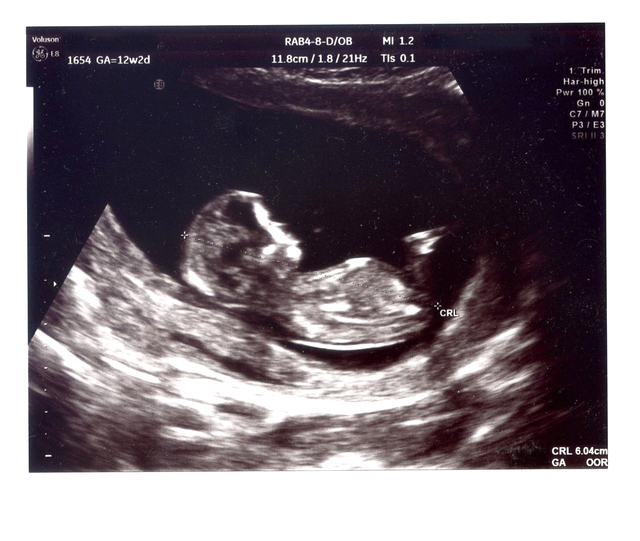

CRLはなに?

CRLは 頭殿長(とうでんちょう)をあらわす略号。Crown(頭頂) Rump(お尻) Length(長さ)の頭文字をとったものです。

胎児の頭の先からお尻までの長さをあらわすもので、赤ちゃんの身長、とも言える数値になっています。妊娠初期は個体差の少ない妊娠初期に、この長さを測って出産予定日を確認します。